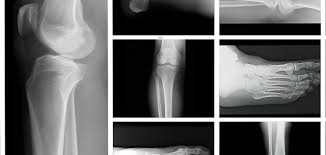

يحتوي تطبيق تصنيف العظام على جميع أنظمة تصنيف كسور العظام مثل تصنيف كسور الرأس العضدي (تصنيف Neer) وتصنيف أمراض العظام مثل تصنيف تنخر عظم الفخذ (تصنيف Vicat).

كما تم تصنيف كل قسم حسب المناطق التشريحية (الكتف - الكوع - الرسغ واليد - الحوض والورك - الركبة - الكاحل والقدم).

تم تقديم التصنيف بإيجاز عن طريق الجداول بطريقة سهلة الفهم ومزود بالتخطيط والأشعة السينية.